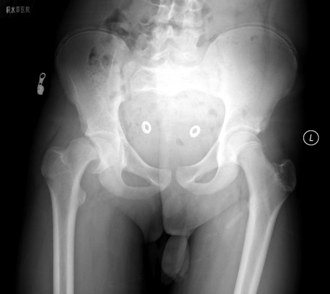

病例1 男,13岁,左侧重度SCFE

病例1 髋关节外科脱位,改良Dunn截骨,术后2年,X线示位置良好,无股骨头缺血坏死

1998年,北京积水潭医院小儿骨科在国内首先报道使用Russell牵引结合内固定治疗股骨头骺滑脱,在文中提出“对于急性滑脱,持续牵引逐渐内旋复位是可能的”;2012年开始应用髋关节外科脱位改良Dunn截骨来治疗重度SCFE;2018年在前期工作的基础上,开展应用股骨头骺内血供监测来实时监控术中股骨头骺血供;2019年开始应用在机器人辅助下行重度SCFE的经皮螺钉固定,并承担北京市医管中心专项项目:中重度股骨头骺滑脱治疗的临床研究。

病例2 男,14岁,右侧重度SCFE,行闭合复位,经皮空心钉固定术

病例2 术后17个月复查,X线示位置良好,无股骨头缺血坏死发生